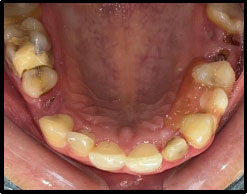

A 34-year-old female patient presented to the Department of Prosthodontics and Crown & Bridge at Santosh Dental College and Hospital, Ghaziabad, following a traumatic fall. Her chief complaint was a fractured maxillary anterior tooth accompanied by compromised facial esthetics. The patient had no previous restorative or endodontic treatment on the affected tooth and maintained satisfactory oral hygiene. Clinical examination revealed no evidence of pain, swelling, or associated soft-tissue pathology. Intraoral evaluation identified an Ellis Class III fracture involving the maxillary left lateral incisor (tooth 22), as illustrated in Fig. (1). Radiographic assessment revealed loss of tooth structure involving the enamel and dentin with pulpal involvement. Pulp vitality testing further confirmed that the tooth was non-vital. The traumatic incident was isolated, and this clinical context guided our decision to use a conservative, adhesive fiber post-and-core system to preserve residual tooth structure.

PRE-operative.